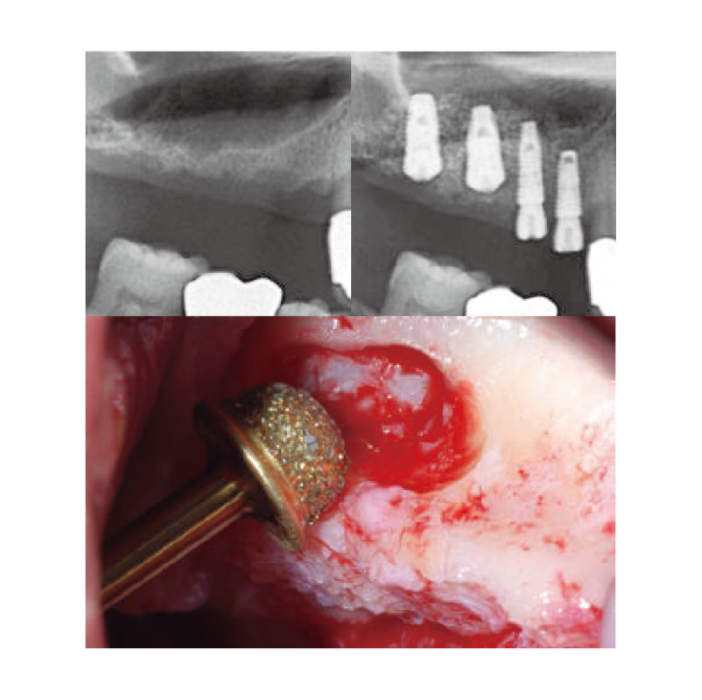

Thin-out Technique

Thin-out Technique -